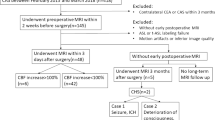

A total of 25 patients who were operated for moyamoya disease from May 2017 to November 2018 were included in the study. All the patients with clinical symptoms of occlusive vascular disease were diagnosed as MMD based on imaging findings. These patients were admitted for revascularisation surgery. All the patients underwent routine preoperative MRI with ASL perfusion sequence to assess baseline CBF status within a week before surgery.

Follow-up imaging

Out of the 25 patients (26 hemispheres) operated upon, unilateral revascularisation was done in 24 patients and bilateral in 1 patient. Eleven patients underwent surgery on the right hemisphere and 13 patients on the left side. A combined procedure (STA-MCA bypass with EDAMS) was the most commonly performed surgery in our series (22/26 hemispheres). Only the STA-MCA bypass was done in 4 patients. The most common reason for combined procedure in such patients was inadequate calibre of the donor (STA) or recipient artery (MCA branch) on that side. No surgery related complications were encountered in any patient. Clinically cerebral hyperperfusion syndrome (CHPS) was suspected based on acute onset of symptoms like moderate to severe headache, seizures or focal neurological deficits in the postoperative period. Five patients had moderate to severe headache that started mostly on the first/second postoperative days and subsided within 3–4 days; 4 had a mild headache, 3 patients had a single episode of seizures, and 2 patients had a mild fever for which only symptomatic management was done (Table 2). Careful vital monitoring with blood pressure control to prevent postoperative bleed secondary to anastomosis in chronically ischemic territory. No mortality occurred during the prospective study period. Postoperative MRI with TOF MR angiography and ASL perfusion was done in all 25 patients to look for postoperative bleed, acute infarct and patency of anastomosis. One patient who was operated on the left side and had an episode of seizures post-surgery was found to have right high parietal infarct. Three patients had a small area of diffusion restriction at the anastomotic side. Apart from the postoperative changes, no postoperative bleed was seen in any of the patients. There was a statistically significant increase (P < 0.05) in postoperative nCBFh values in the frontal, temporal and parietal regions but not in the basal ganglia (Table 3).On imaging, a normal increase in perfusion was defined as an increase in nCBF values to 30–100% as compared to the pre-operative levels without any clinical deficit. The possibility of cerebral hyperperfusion was kept whenever the percentage increase in nCBF values were more than 100% of preoperative nCBFh or nCBFcbl values on the operated site, either in the fronto-temporo-parietal region or basal ganglia in the absence of obvious infarcts or postoperative collections. ASL showed more than 100% increase in nCBFh and nCBFcbl in 11 patients, but only 5 patients had significant postoperative symptoms. The remaining 6 patients where ASL showed raised nCBFh or nCBFcbl values had only mild symptoms like mild headache and low grade fever. No seizures or focal neurological deficits were seen in these patients. These patients were managed conservatively with appropriate control of blood pressure and frequent clinical examinations. None of these had any deficits on follow-up after 3 months.

Case 1

Case 2

Case 3